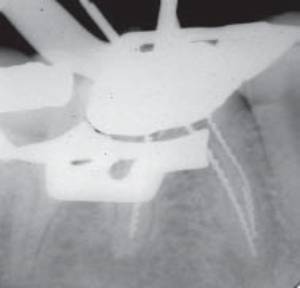

4-в первую очередь, постараться напрямую обойти сломанный фрагмент, очень

аккуратно используя ручные инструменты. Зто техника называется «Ву Pass»

Процедура прохождение рядом со сломанным инструментом. Такая

процедура позволяет нам очистить канал апикальнее и тем самым решить проблему